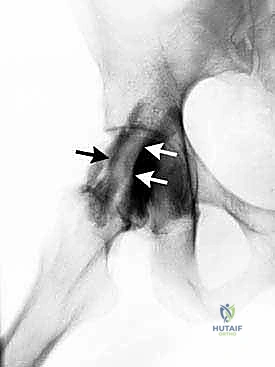

- الأشعة السينية (X-rays): لاستبعاد وجود كسور، التهاب مفاصل (خشونة)، أو تشوهات عظمية (مثل الاصطدام الفخذي الحُقي).

- الموجات فوق الصوتية الديناميكية (Dynamic Ultrasound): أداة ممتازة لأنها تسمح للطبيب برؤية حركة الأوتار مباشرة أثناء قيام المريض بالحركة التي تسبب الطقطقة، مما يؤكد التشخيص الفوري لالتهاب الأوتار أو الجراب.

- التصوير بالرنين المغناطيسي (MRI) أو (MR Arthrogram): هو المعيار الذهبي لتشخيص النوع داخل المفصلي. يوفر صورًا عالية الدقة للغضاريف، الشفة الحرقفية، والأنسجة الرخوة. يتم حقن صبغة داخل المفصل أحيانًا لإبراز التمزقات الدقيقة.